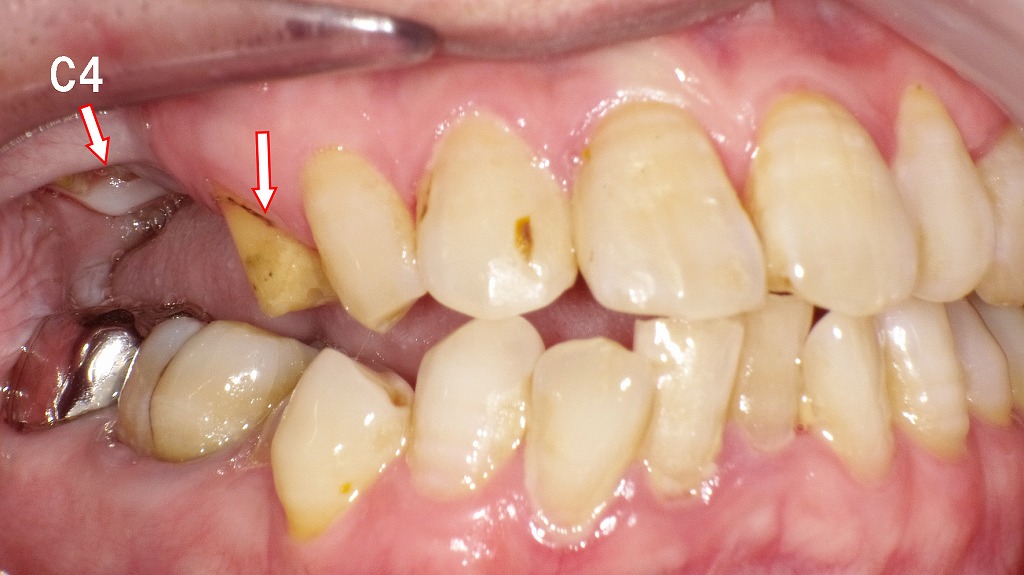

🚨銀歯(ブリッジ)が取れて放置した症例

この画像は、上顎右側の口腔内写真です。以下のように説明できます。

🦷 状況の概要

- 右上4番・5番・6番に装着されていた保険のブリッジが脱離しています。

- 右上4番(第一小臼歯)は生活歯で、歯質は健全に保たれています。

- 一方、右上6番(第一大臼歯)は、被せ物の内部で虫歯が進行し、C4(歯冠崩壊)の状態になっています。

🔍 詳細な所見

- 右上4番:歯冠が健全に残り、歯髄反応のある生活歯。支台歯として再利用可能。

- 右上5番:すでに欠損しているためブリッジのポンティックとして対応。

- 右上6番:金属冠が外れた後、歯根が露出し、内部に深い虫歯を確認。歯質が大きく失われており、抜歯が必要な状態。

⚠️ 臨床的判断

- 右上6番はC4の虫歯であり、保存不可能な可能性が高い。抜歯後はインプラント、部分入れ歯などの補綴的対応が必要です。

- 右上4番は健全なため、単冠の支台歯として再利用できる見込みがあります。